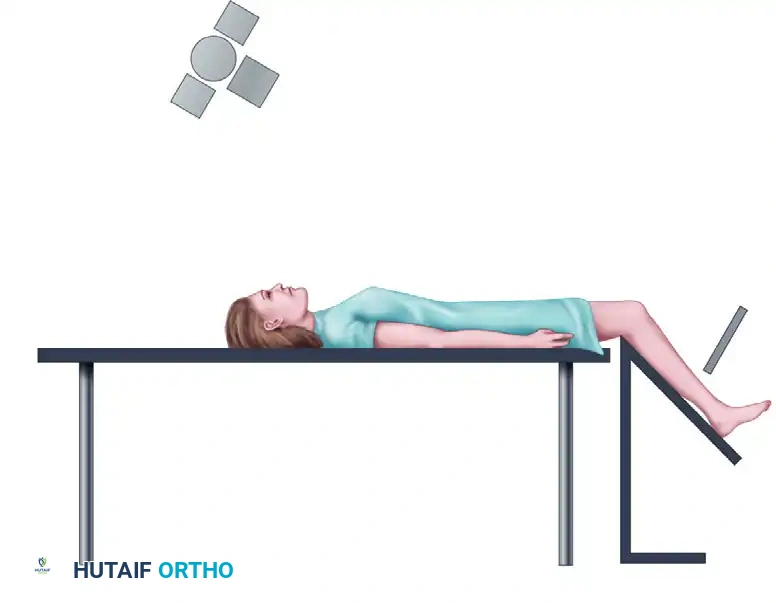

Standard and Specialized Positioning Techniques

Proper patient positioning is paramount for obtaining reproducible and diagnostically accurate radiographs of the patellofemoral joint.

1. Infrapatellar View Positioning:

This technique is utilized to assess the inferior pole of the patella and the patellar tendon footprint.

2. Axial View Positioning:

The axial view is critical for assessing the dynamic tracking of the patella within the trochlear groove. The knee is typically flexed to 30 or 45 degrees.

3. Skyline View Positioning:

The skyline view provides a tangential perspective of the patellofemoral articulation, allowing the surgeon to evaluate the medial and lateral facets, the depth of the trochlear sulcus, and the presence of marginal osteophytes.